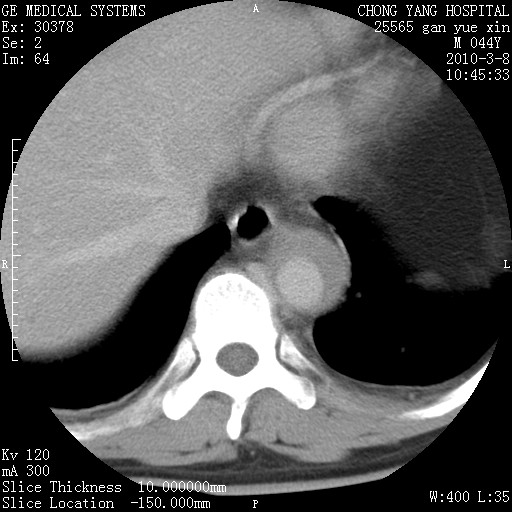

标题: CT24940:主动脉增强,典型病例。 [打印本页]

标题: CT24940:主动脉增强,典型病例。

夹层动脉瘤。

动脉夹层

夹层动脉瘤,典型

主动脉夹层。

动脉夹层的分型:

⒈debakey分型:根据主动脉夹层累及部位,分为三型:ⅰ型:原发破口位于升主动脉或主动脉弓部,夹层累及升主动脉、主动脉弓部、胸主动脉、腹主动脉大部或全部,少数可累及髂动脉。ⅱ型:原发破口位于升主动脉,夹层累及升主动脉,少数可累及部分主动脉弓。ⅲ型:原发破口位于左锁骨下动脉开口远端,根据夹层累及范围又分为ⅲa,ⅲb。ⅲa型:夹层累及胸主动脉。ⅲb型:夹层累及升主动脉、腹主动脉大部或全部。少数可累及髂动脉。

⒉stanford分型:a型:夹层累及升主动脉,无论远端范围如何。b型:夹层累及左锁骨下动脉开口以远的降主动脉。

夹层动脉瘤,少量胸水

夹层动脉瘤;左侧少量胸腔积液。

典型主动脉夹层。